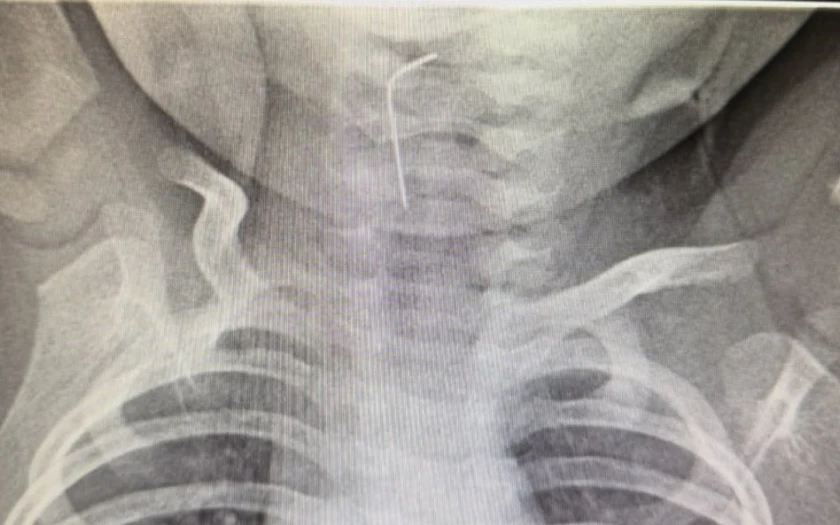

Түркістан облыстық балалар ауруханасына жедел жәрдем қызметі арқылы 9 айлық сәби шұғыл түрде жеткізілді, деп хабарлайды JANABASTAU.KZ ақпарат агенттігі.

Белгілі болғандай, сәби абайсызда ине жұтып қойған.

«Тез арада аурухана мамандары - хирург Темірбеков Мұхагали және эндоскопист Ырысқұлов Бабыр эндоскопиялық әдісті қолдана отырып, рентгенологиялық тексеру жүргізді. Нәтижесінде бөгде заттың нақты орналасқан орнын анықтап, өңеште тұрып қалған бөгде затты сәтті түрде алып шықты», - деп хабарлады Түркістан облысы әкімдігінің баспасөз қызметі.